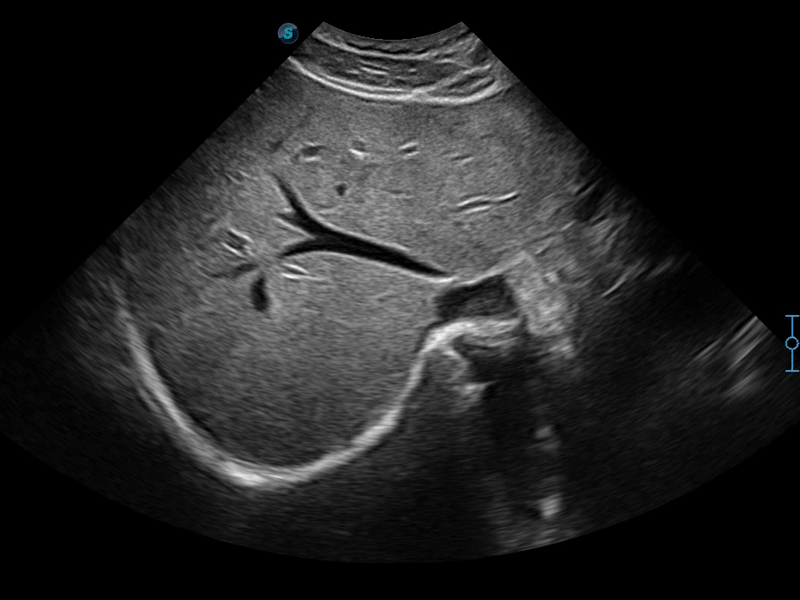

μ-Scan+新一代微米成像技术

新一代微米成像技术大大提高了器官和病变的可见性。高清对比度分辨率将抑制斑点噪声,同时保持真实的组织结构。

临床图像